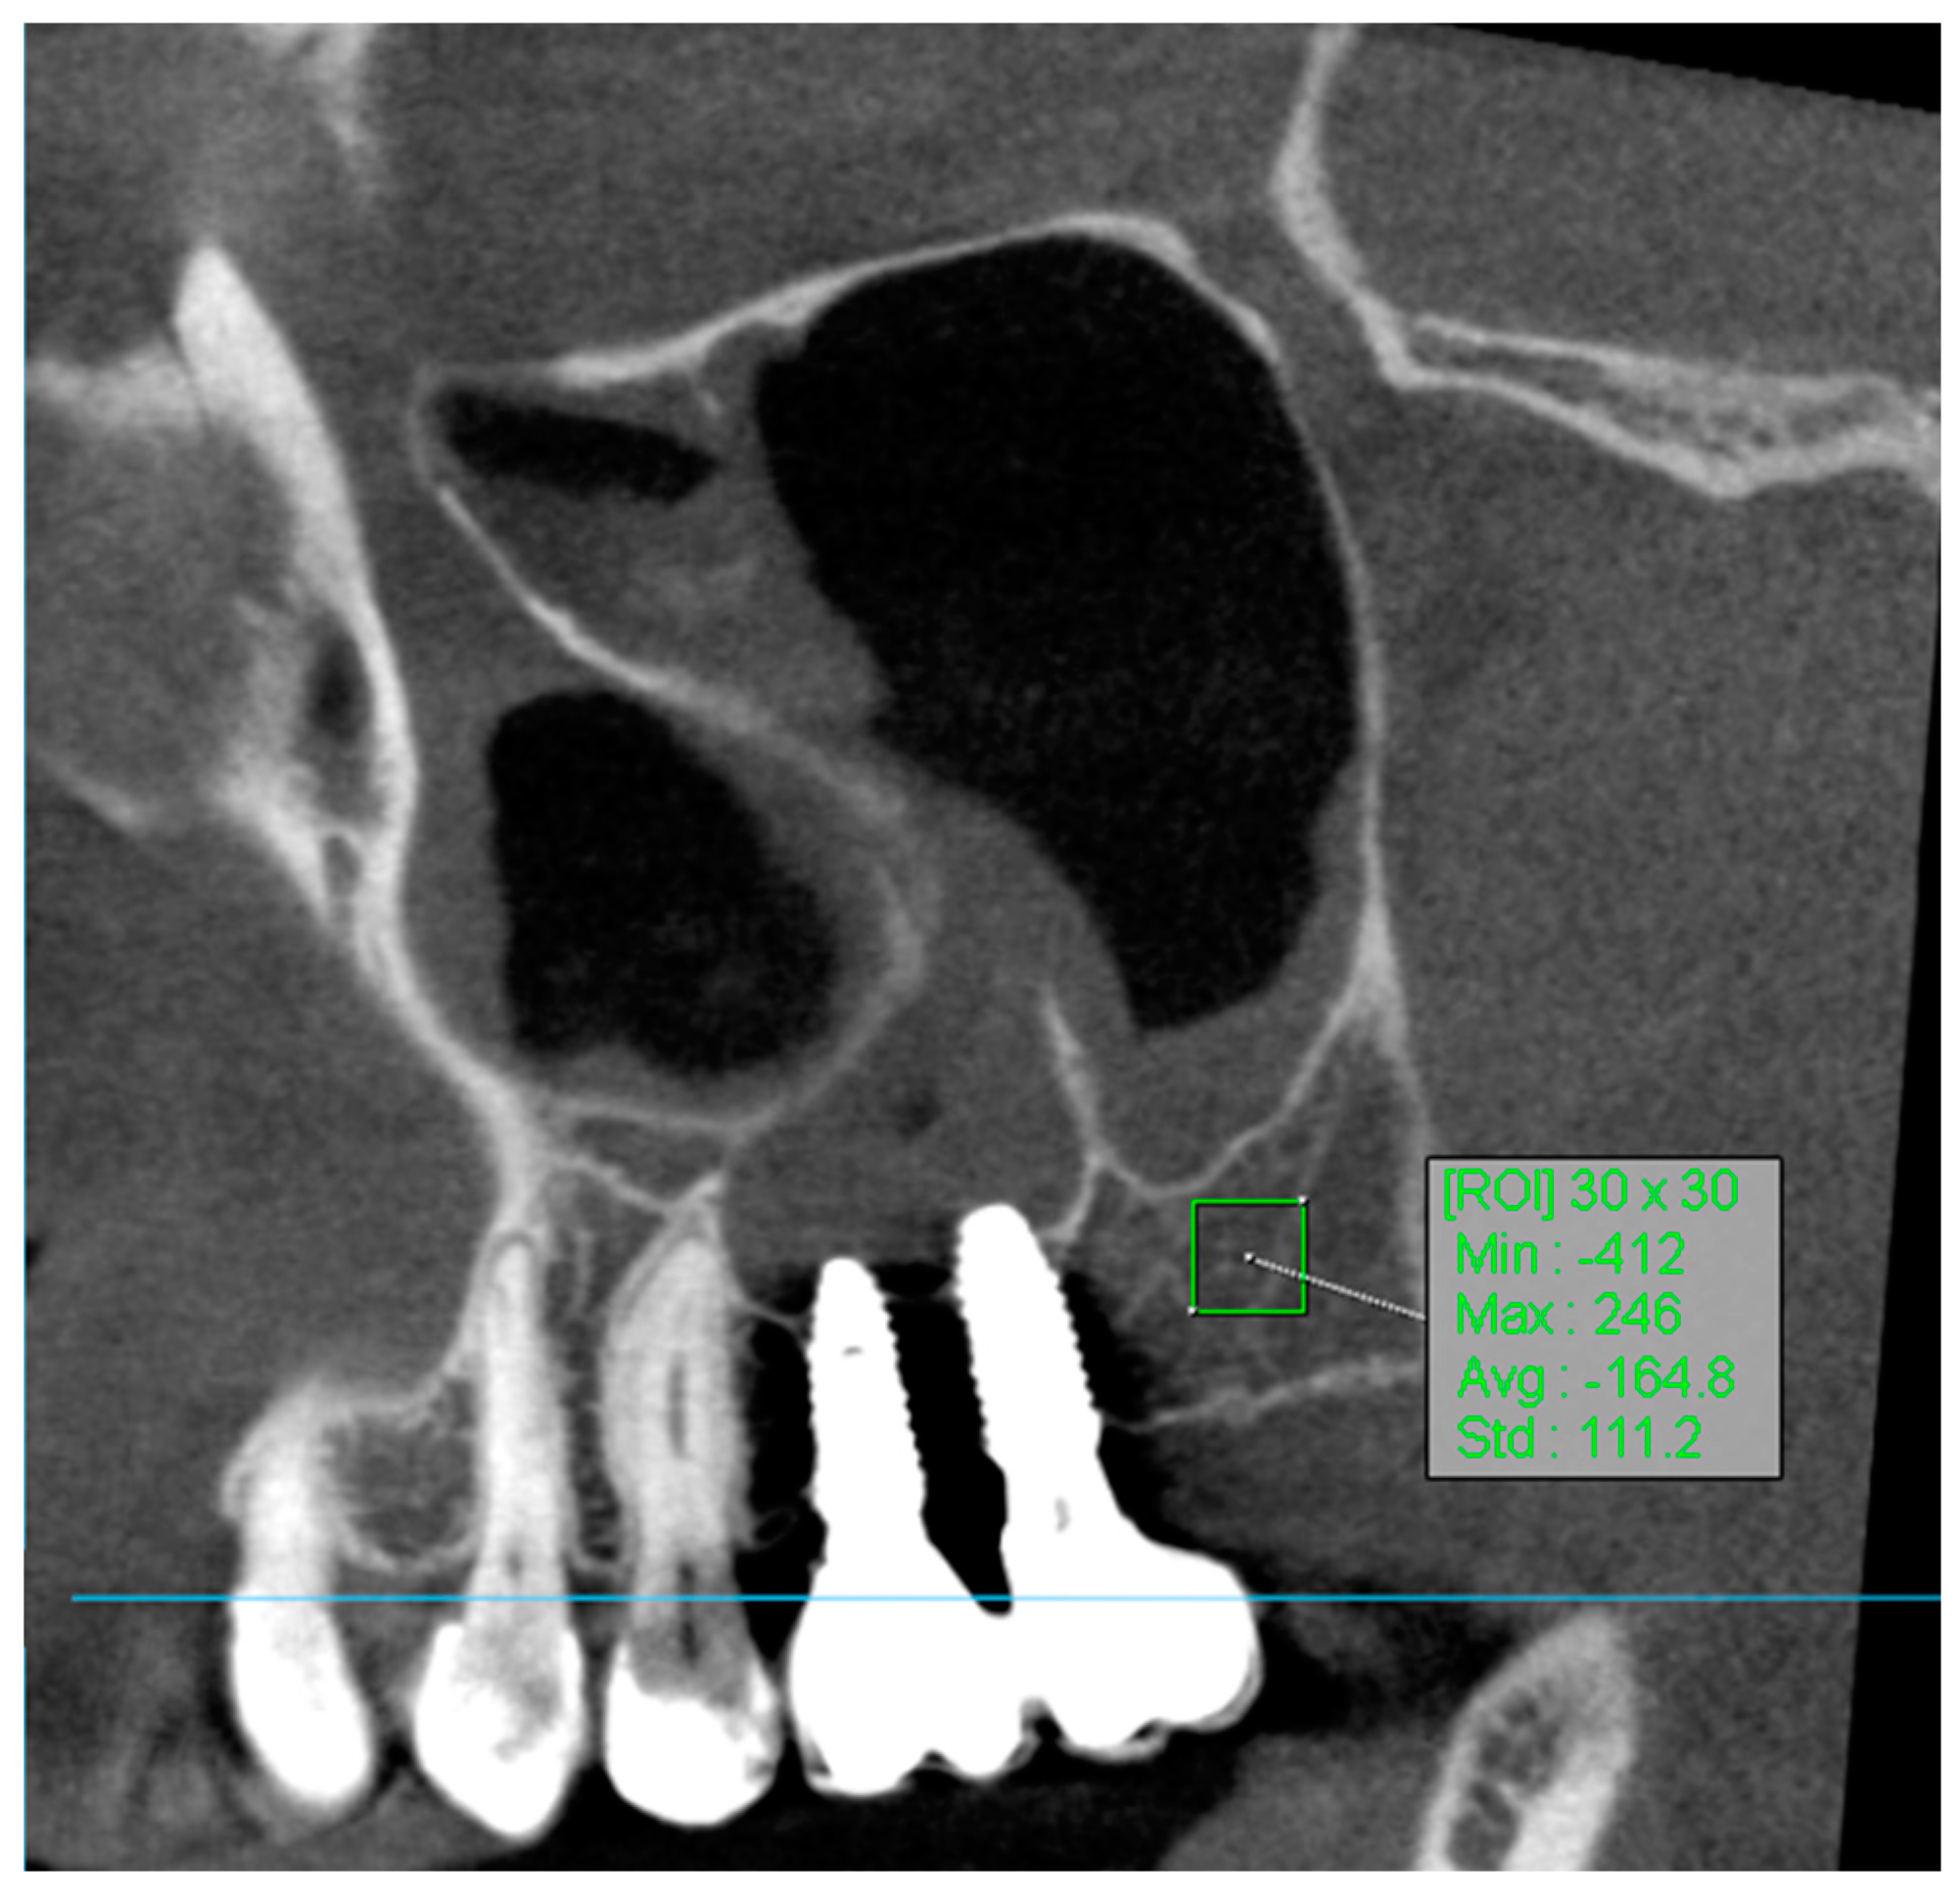

2.4. Assessment of Radiographs and Assessment of Bone Attenuation